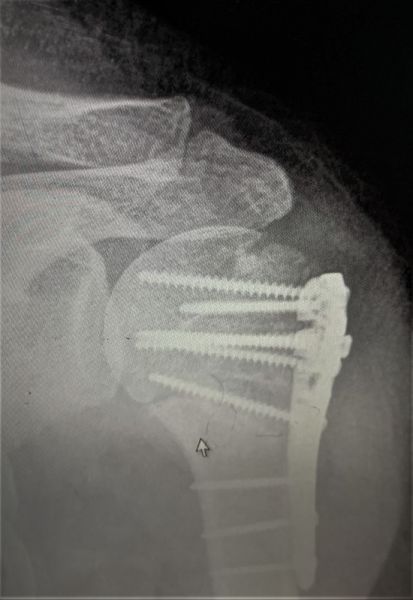

4. Displaced fracture of distal end of the right radius (wrist fracture) in a 63-year-old female.

Treatment. Open reduction internal fixation

I. Before operation, anteroposterior x-ray of the wrist II. Before operation, lateral x-ray of the wrist IIA. Day of procedure, lateral view IIB. Day of procedure, anteroposterior view